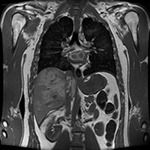

- МРТ органов брюшной полости (обзорное исследование)

- МРТ печени